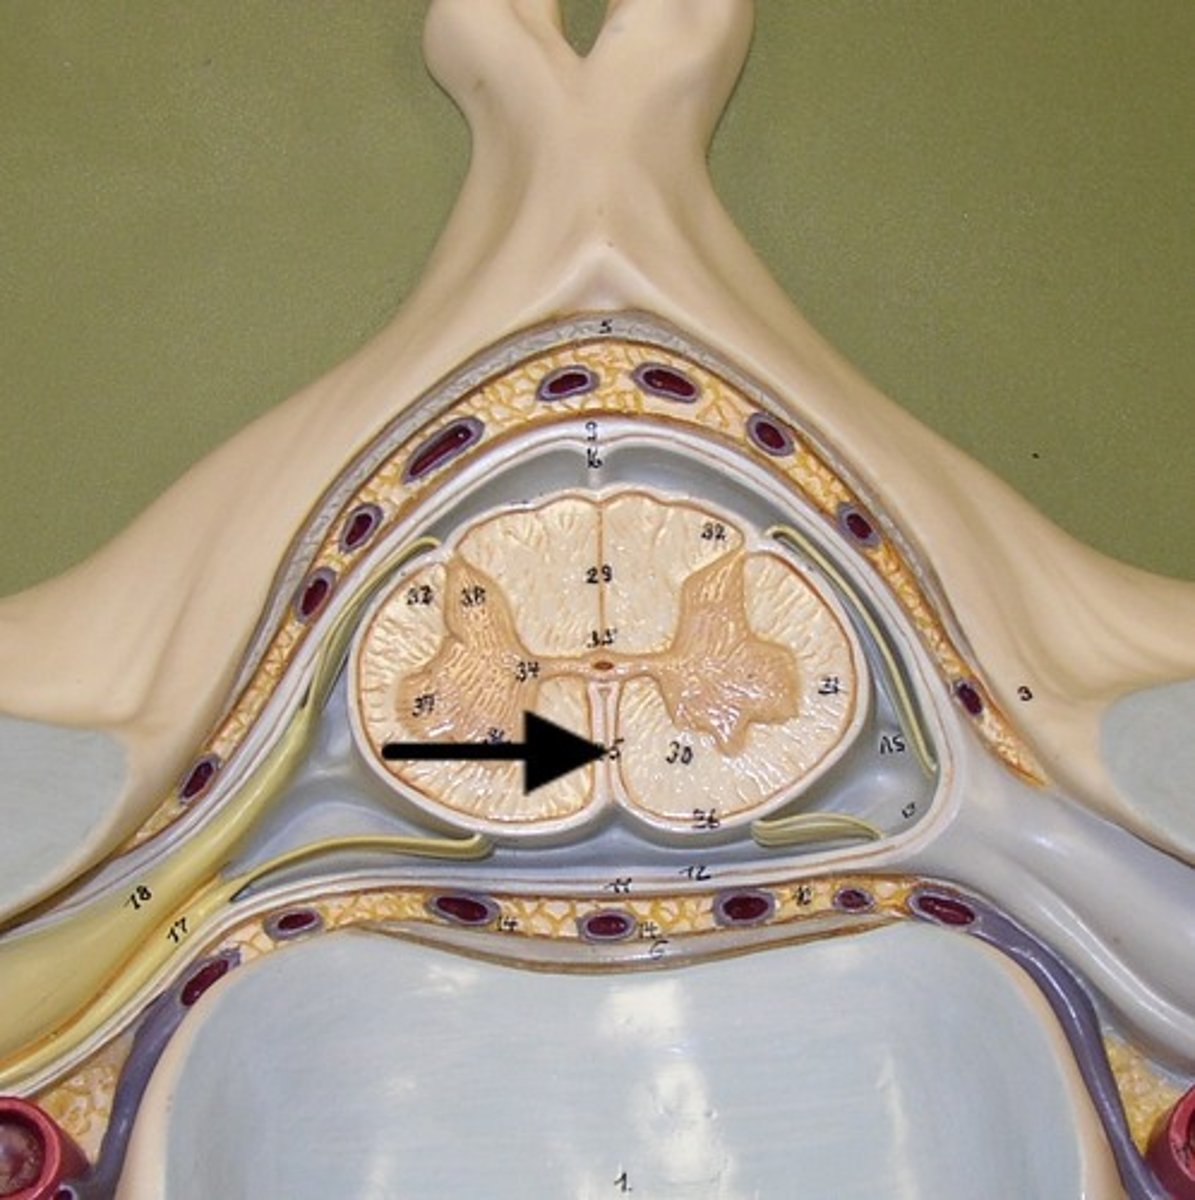

epidural space

dura mater

thick, outermost layer of the meninges surrounding and protecting the brain and spinal cord

subdural space

space between dura mater and arachnoid mater

arachnoid mater

middle layer of the meninges

B on model

subarachnoid space

a space in the meninges beneath the arachnoid membrane and above the pia mater that contains the cerebrospinal fluid

pia mater

the delicate innermost membrane enveloping the brain and spinal cord.

denticulate ligaments

extensions of pia mater that secure cord to dura mater laterally

filum terminale

single thin thread of fibrous tissue at end of conus medullaris in the center that attaches to coccygeal ligament

posterior root

axons of sensory neurons

posterior root ganglion

anterior root

axons of motor neurons

spinal nerve